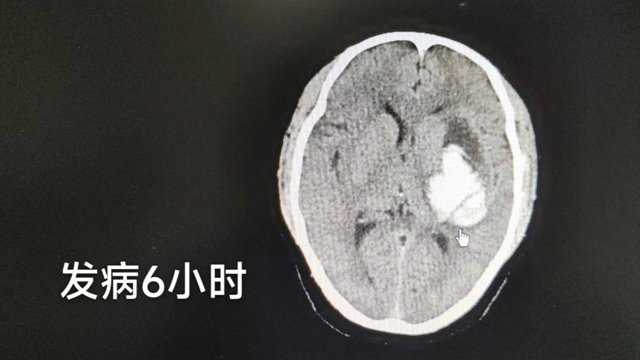

因张老师基础疾病多,距发病6小时再次复查头颅CT提示:左侧基底节区-侧脑室旁血肿,密度不均匀,大小约4.2x6.7cm,左侧脑室受压变窄,中线结构右偏,与发病时比较,脑出血范围增大。查体:GCS评分:7分,右侧肢体肌力1级。

因患者为语文教师,且左侧大脑半球为语言优势半球,考虑到职业特性,顾应江教授团队为其制定了手术方案:微创钻孔引流术,手术半小时左右即可完成,且对脑组织损伤极小,术后苏醒快。